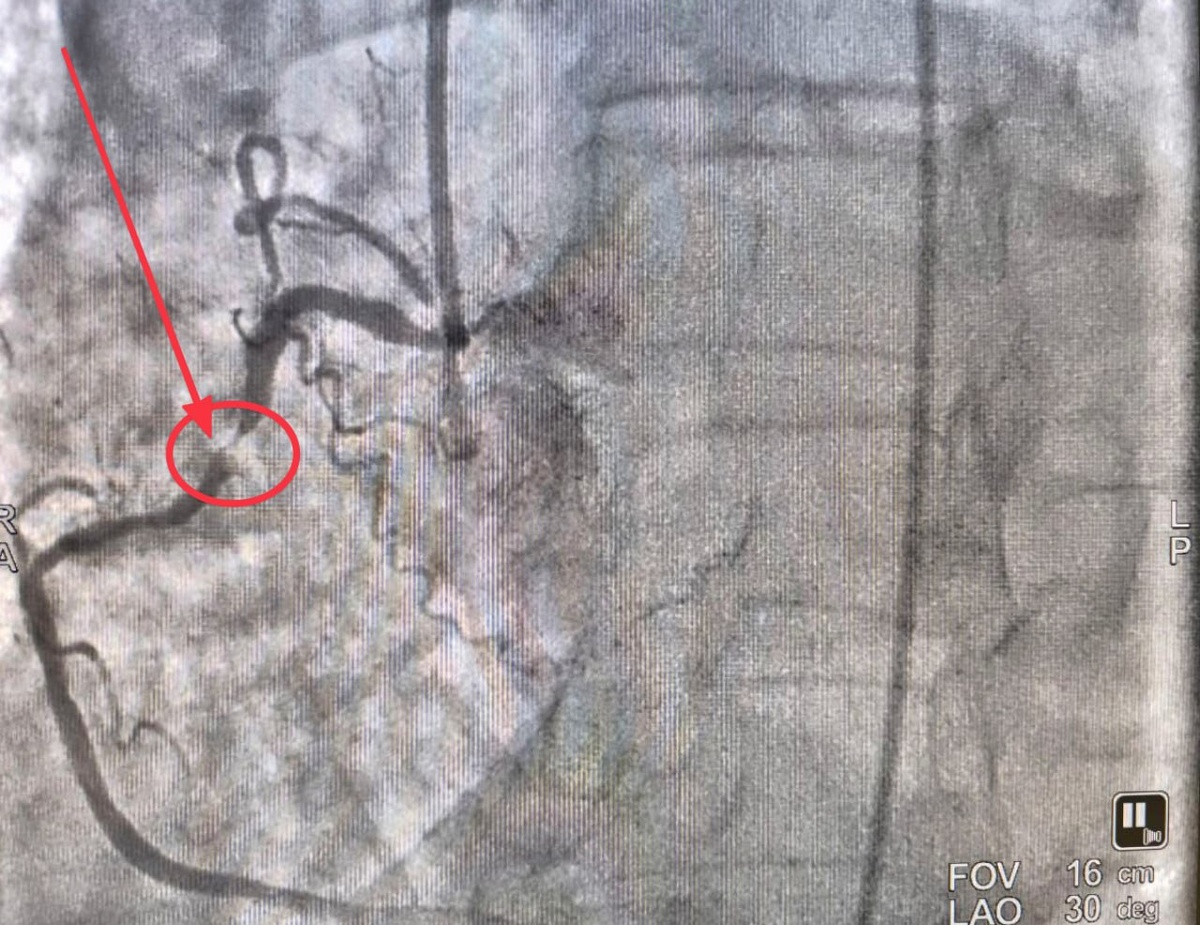

πŸ’Ÿ Π’Π΅Ρ‡Π΅Ρ€ΠΎΠΌ Π½Π°ΠΊΠ°Π½ΡƒΠ½Π΅ Π² ΠΎΡ‚Π΄Π΅Π»Π΅Π½ΠΈΠ΅ рСнтгСнхирургичСских ΠΌΠ΅Ρ‚ΠΎΠ΄ΠΎΠ² диагностики ΠΈ лСчСния РСспубликанской Π±ΠΎΠ»ΡŒΠ½ΠΈΡ†Ρ‹ Π±Ρ‹Π»Π° доставлСна ΠΏΠ°Ρ†ΠΈΠ΅Π½Ρ‚ΠΊΠ° 86 Π»Π΅Ρ‚ с острым ΠΈΠ½Ρ„Π°Ρ€ΠΊΡ‚ΠΎΠΌ ΠΌΠΈΠΎΠΊΠ°Ρ€Π΄Π°.

Команда ΠΊΠ°Ρ€Π΄ΠΈΠΎΠ»ΠΎΠ³ΠΎΠ², Ρ€Π΅Π½Ρ‚Π³Π΅Π½Ρ…ΠΈΡ€ΡƒΡ€Π³ΠΎΠ² ΠΈ анСстСзиологов-Ρ€Π΅Π°Π½ΠΈΠΌΠ°Ρ‚ΠΎΠ»ΠΎΠ³ΠΎΠ² ΠΏΡ€ΠΎΠ²Π΅Π»Π° ΡΠΊΡΡ‚Ρ€Π΅Π½Π½ΡƒΡŽ Π±Π°Π»Π»ΠΎΠ½Π½ΡƒΡŽ ангиопластику ΠΈ стСнтированиС ΠΊΠΎΡ€ΠΎΠ½Π°Ρ€Π½ΠΎΠΉ Π°Ρ€Ρ‚Π΅Ρ€ΠΈΠΈ. ЦСль β€” Π²ΠΎΡΡΡ‚Π°Π½ΠΎΠ²ΠΈΡ‚ΡŒ кровоснабТСниС сСрдца ΠΈ ΠΌΠΈΠ½ΠΈΠΌΠΈΠ·ΠΈΡ€ΠΎΠ²Π°Ρ‚ΡŒ послСдствия ΠΈΠ½Ρ„Π°Ρ€ΠΊΡ‚Π°.